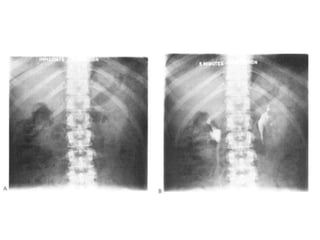

Fig. The KUB. (A) Full length and (B) cross kidney films

Fig. The KUB.(A) Full length and (B) cross kidney films